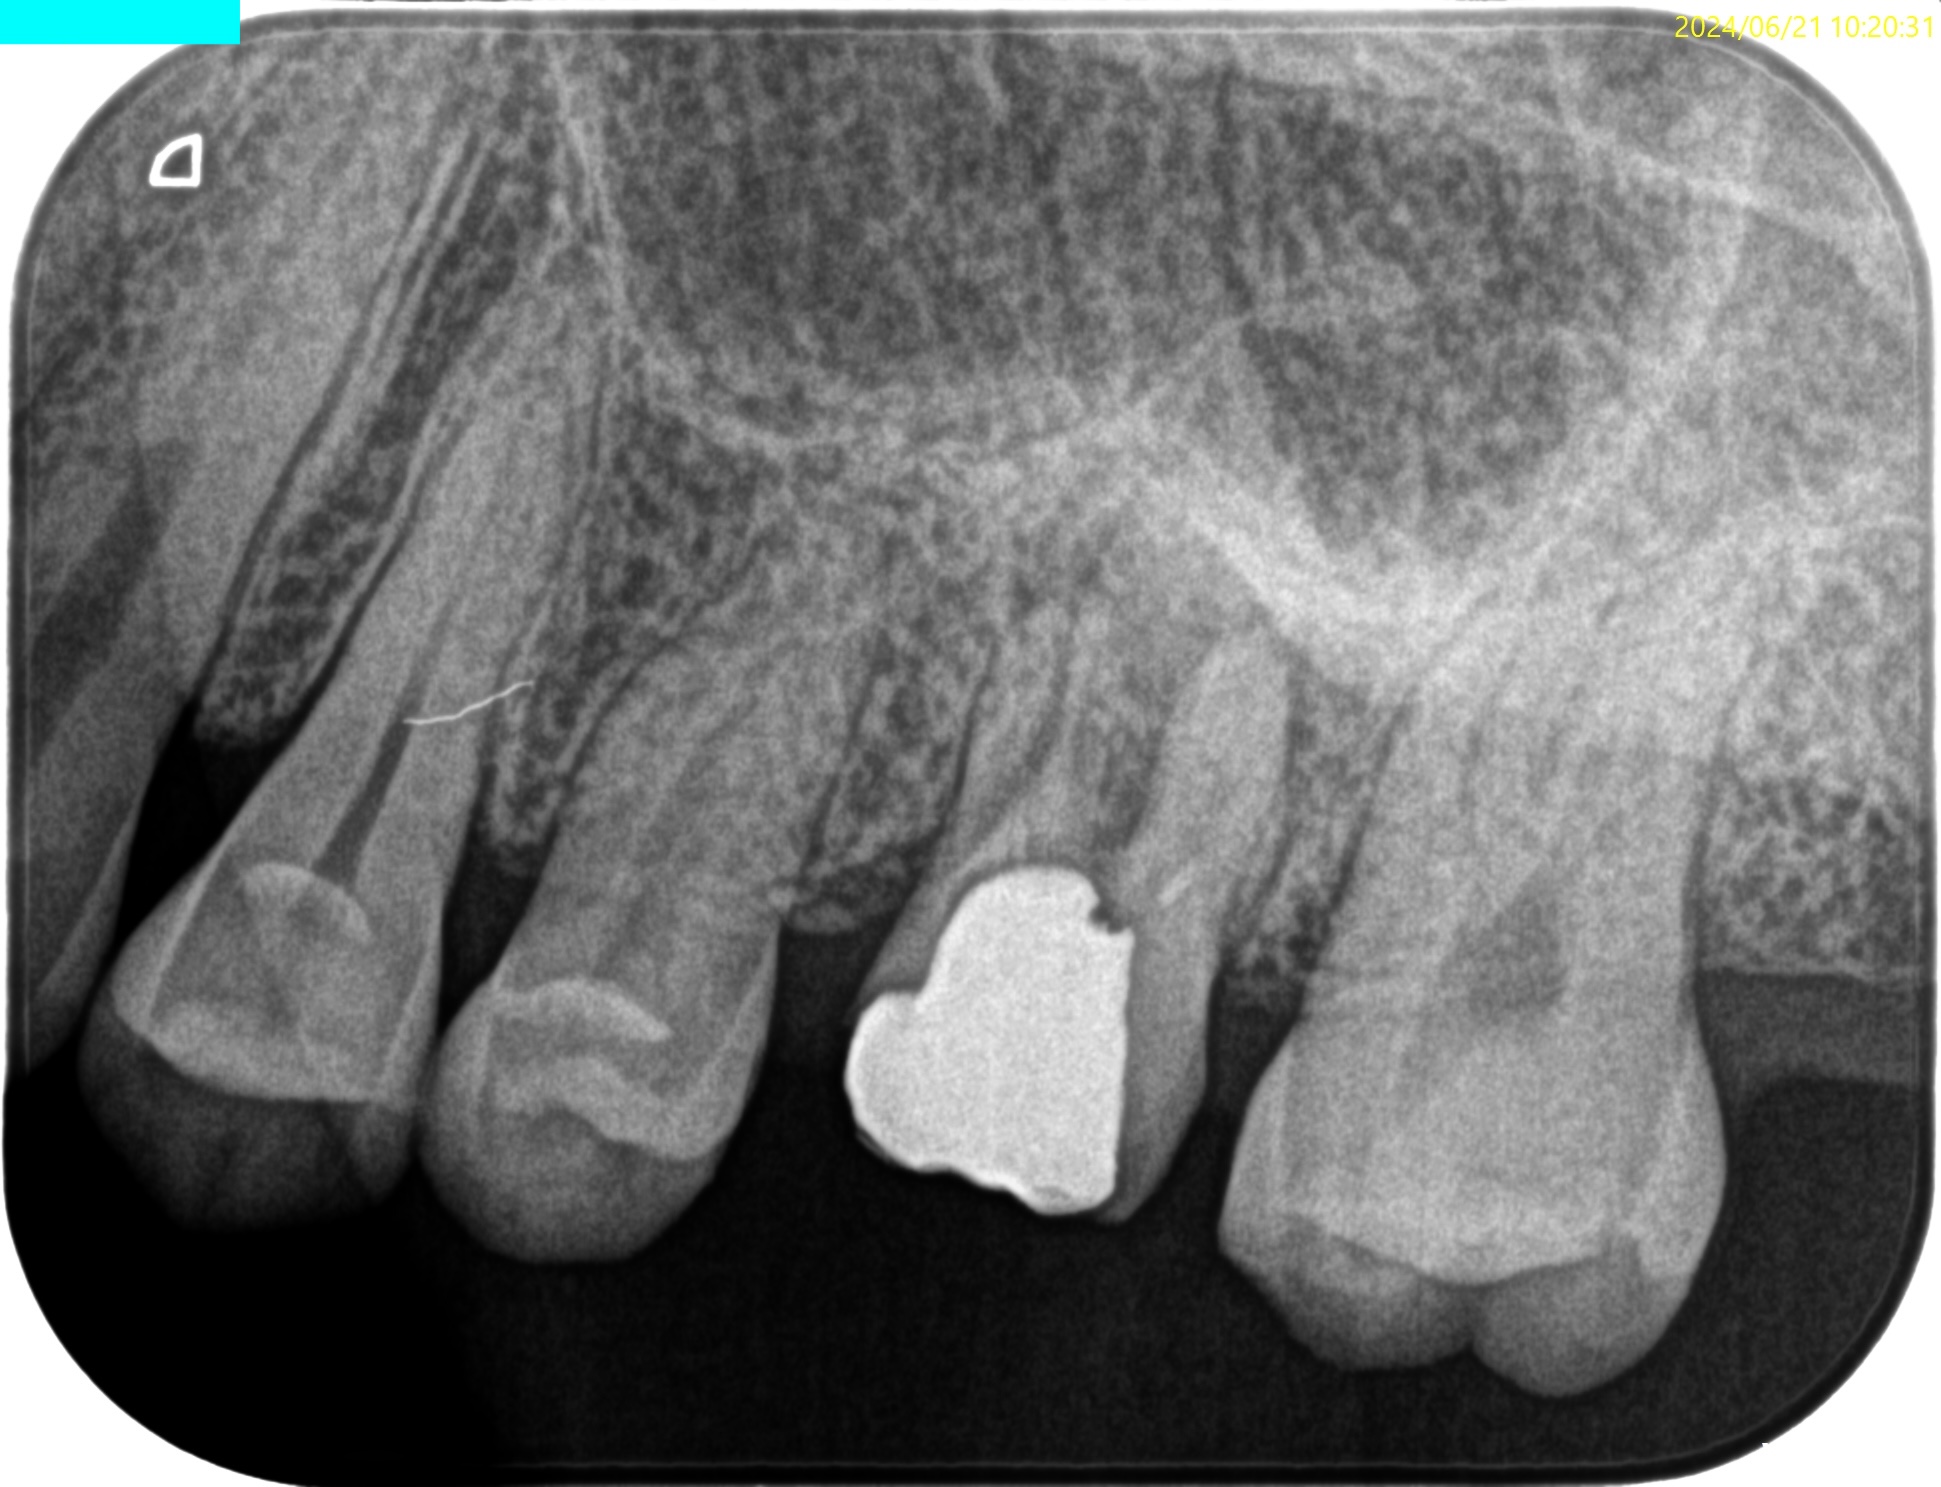

PA(2024.6.21)

Pulp Dx: Previously initiated therapy

Periapical Dx:Symptomatic apical periodontitis

Recommended Tx: RCT